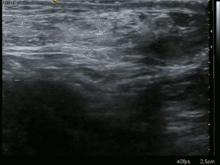

Ultrasound image of inguinal hernia. Moving intestines in inguinal canal with respiration.

Medical imaging

A physician may diagnose an inguinal hernia, as well as the type, from medical history and physical examination.[20] For confirmation or in uncertain cases, medical ultrasonography is the first choice of imaging, because it can both detect the hernia and evaluate its changes with for example pressure, standing and Valsalva maneuver.[21]